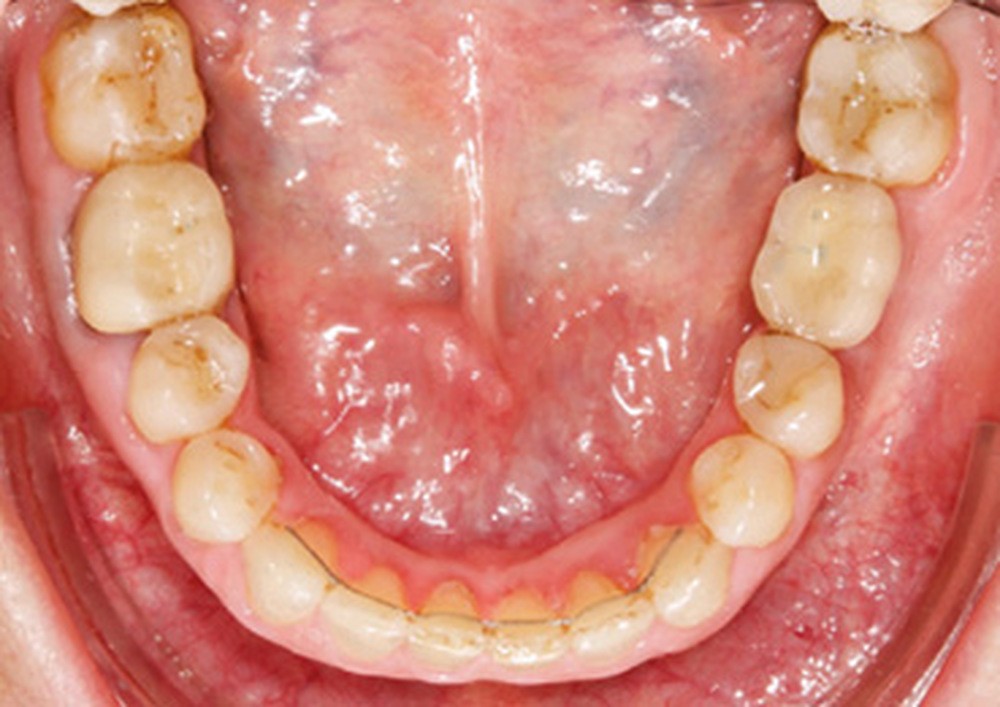

Examen endobuccal (fig. 2a-e)

L’arcade maxillaire est asymétrique et parabolique. Elle présente une mésio-position du secteur 1. On note des rotations mésio-vestibulaire de 13 et disto-vestibulaire de 23 et une palato-version incisive. Les restaurations prothétiques sur 11, 16 et 24 semblent à refaire. L’arcade mandibulaire est asymétrique et parabolique avec une couronne sur implant en 36.

Dans la dimension transversale, on constate une endoalvéolie maxillaire. Dans la dimension sagittale, on observe une classe II plus importante à droite où elle est complète de 5 mm. Le surplomb est absent et la supraclusion totale (6 mm) par supra-alvéolie mandibulaire.